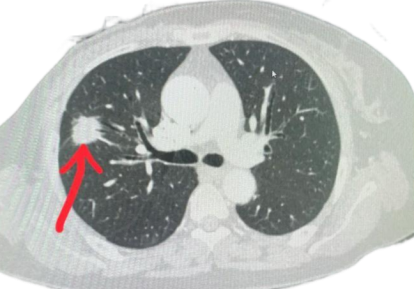

五、怀疑肺癌时常用的检查方法有哪些?

目前常用的有效检查方法包括胸部CT扫描、支气管镜、胸腔镜、胸膜活检、经皮肺穿刺活检、痰或胸水脱落细胞检查等,医师会根据具体病情选择相应的检查方法,必要时做开胸肺活检。注意胸片容易漏诊,不能代替胸部CT。

六、肺结节是肺癌吗?发现肺结节该怎么办?

肺结节是指肺内直径<3 cm的局灶性、类圆形、密度增高的实性或亚实性肺部阴影。可孤立或多发,不伴肺不张、肺门淋巴结增大和胸腔积液。引起肺结节的原因有很多,包括肿瘤,感染,长期接触粉尘,免疫功能低下等。其中大多数为良性结节,预后良好,只有2%-10%是早期肺癌。

2.筛查技术:16排以上胸部低剂量螺旋CT(LDCT)可显著提高肺癌的检出率并降低肺癌相关死亡率,具有较高的灵敏度和特异度。不推荐胸部X线、PET-CT及磁共振等进行肺癌筛查。